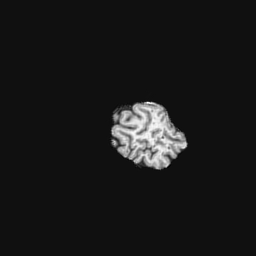

Exp. 2: Fetal brain data is used to test the robustness of our approach under real conditions. Fetuses younger than 30 weeks very often move a lot during examination. Fast MRI sequences allow artifact free acquisition of individual slices but motion between slices corrupts consistent 3D information. Fig. 3 shows that our method is able to accurately predict Ti^^subscript𝑇𝑖\hat{T_{i}} also under these conditions. For this experiment we use ωisubscript𝜔𝑖{\omega_{i}} from three orthogonally overlapping stacks of ssFSE slices covering the fetal brain with approximately 20-30 slices each. We are ignoring the stack transformations relative to the scanner and treat each ωisubscript𝜔𝑖{\omega_{i}} individually. For ΩtrainsubscriptΩ𝑡𝑟𝑎𝑖𝑛\Omega_{train}, 28 clinically approved motion compensated brain reconstructions are resampled into a 150×150×150150150150150\times 150\times 150 volume with 1mm×1mm×1mm1𝑚𝑚1𝑚𝑚1𝑚𝑚1mm\times 1mm\times 1mm spacing. A density of 500 unique sampling normals has been chosen via the Fibonacci sphere sampling method with 25 sampling planes evenly spaced between -25 to +25 on the Z-axis. This gives a plane spacing of 2mm, sampling only the middle portion of the fetal brain. Training took approximately 10hrs for 30 epochs. Prediction, i.e., the forward pass through the network, takes approx. 12 ms/slice.

Figure 3: Comparison of a single slice from a heavily motion corrupted stack of ssFSE T2 weighted fetal brain MRI (a); axial multi planar reconstruction of one sagittal input stack (b); a slice at approximately the same position through a randomly selected training volume (c); failed reconstruction attempt using standard SVR based on three orthogonal stacks of 2D slices (d) (the fetus moved heavily between the acquisition of the individual stacks); reconstruction based on SVRNet Ti^^subscript𝑇𝑖\hat{T_{i}} regression (e); SVR initialised with SVRNet transformations after eight iterations of SVR (f). Note that (e) and (f) are reconstructed directly in canonical atlas co-ordinates.